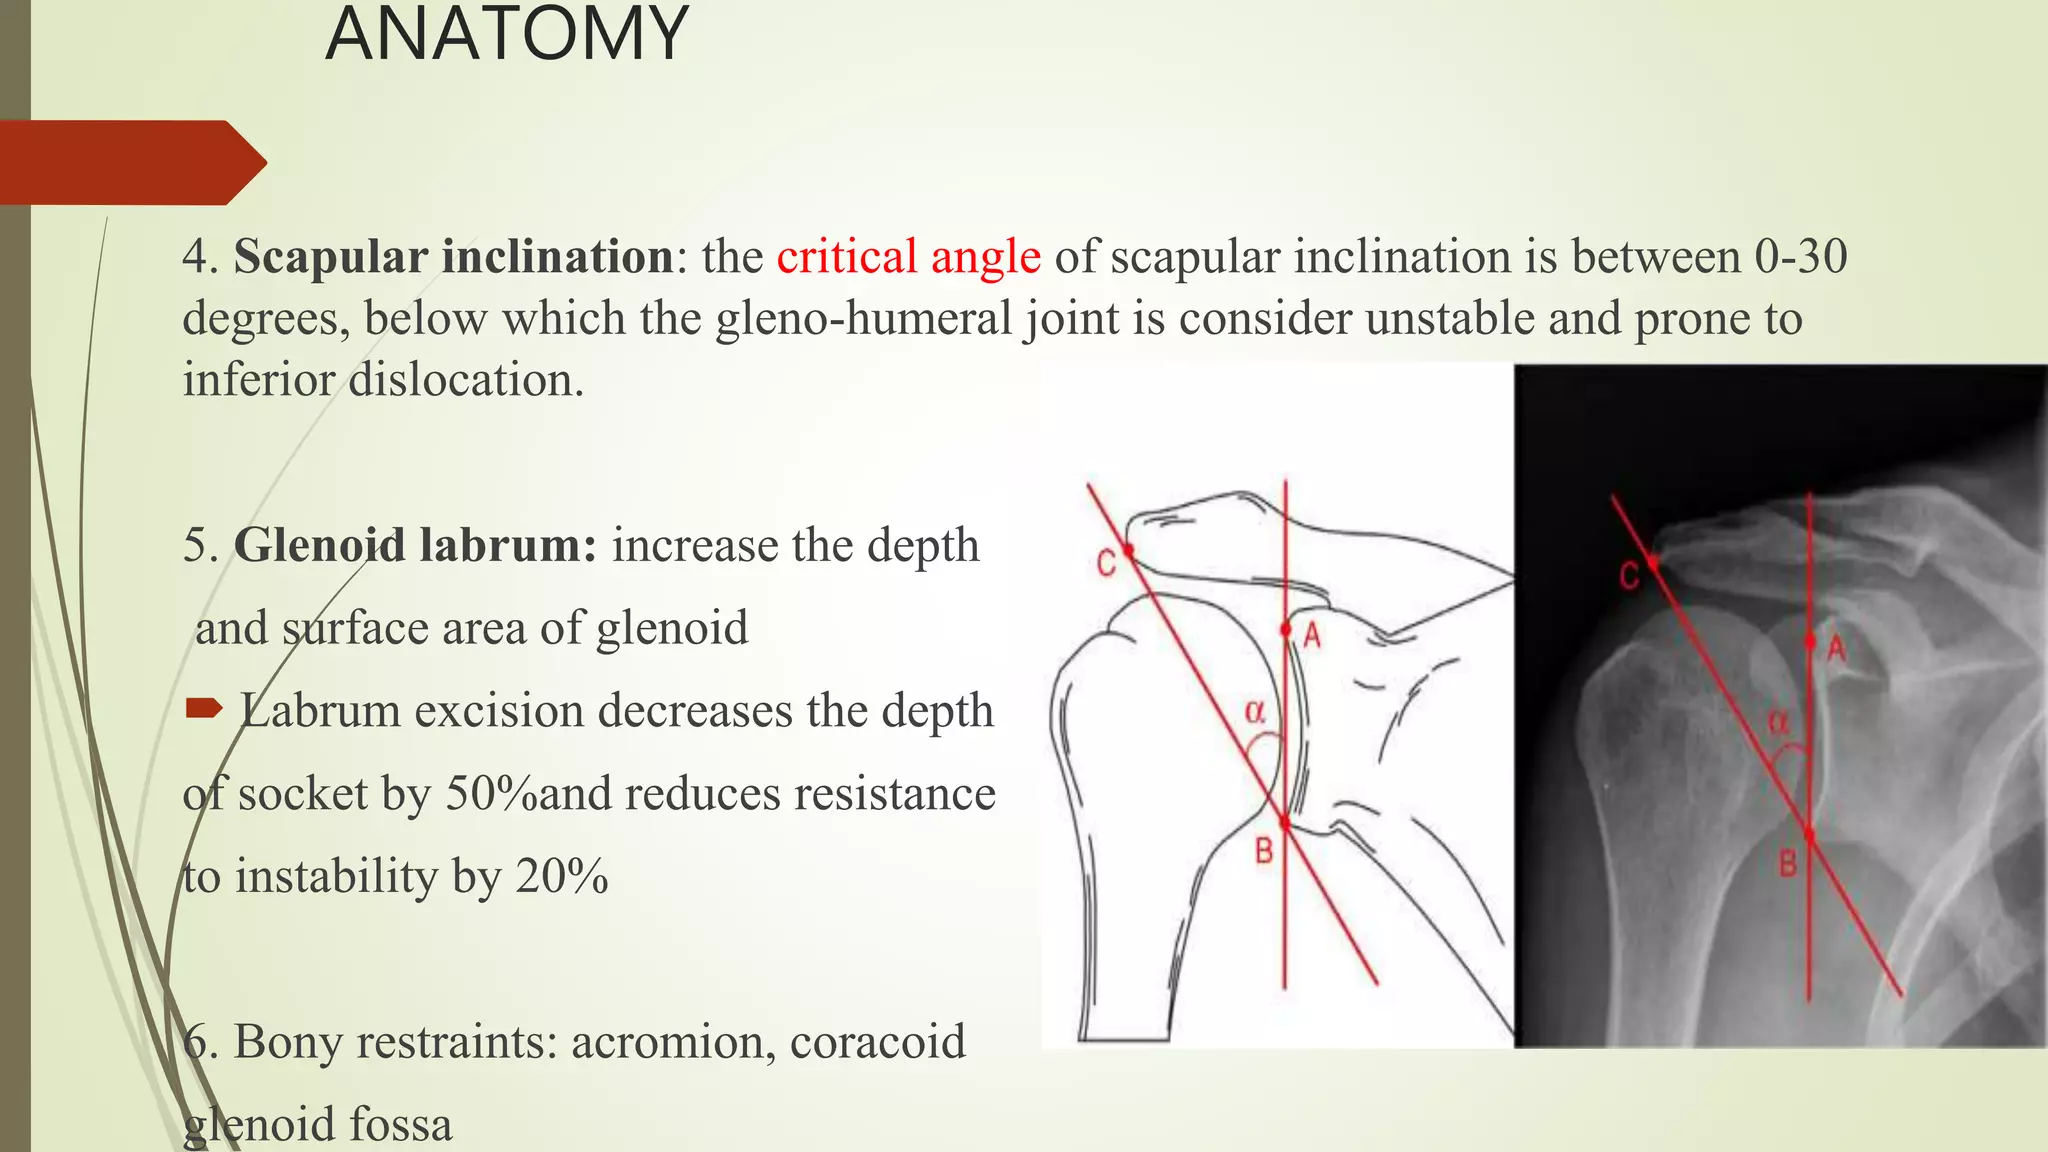

- The shoulder joint is inherently unstable due to its anatomy, relying on both passive structures like the labrum and ligaments as well as active stabilizers like muscles.